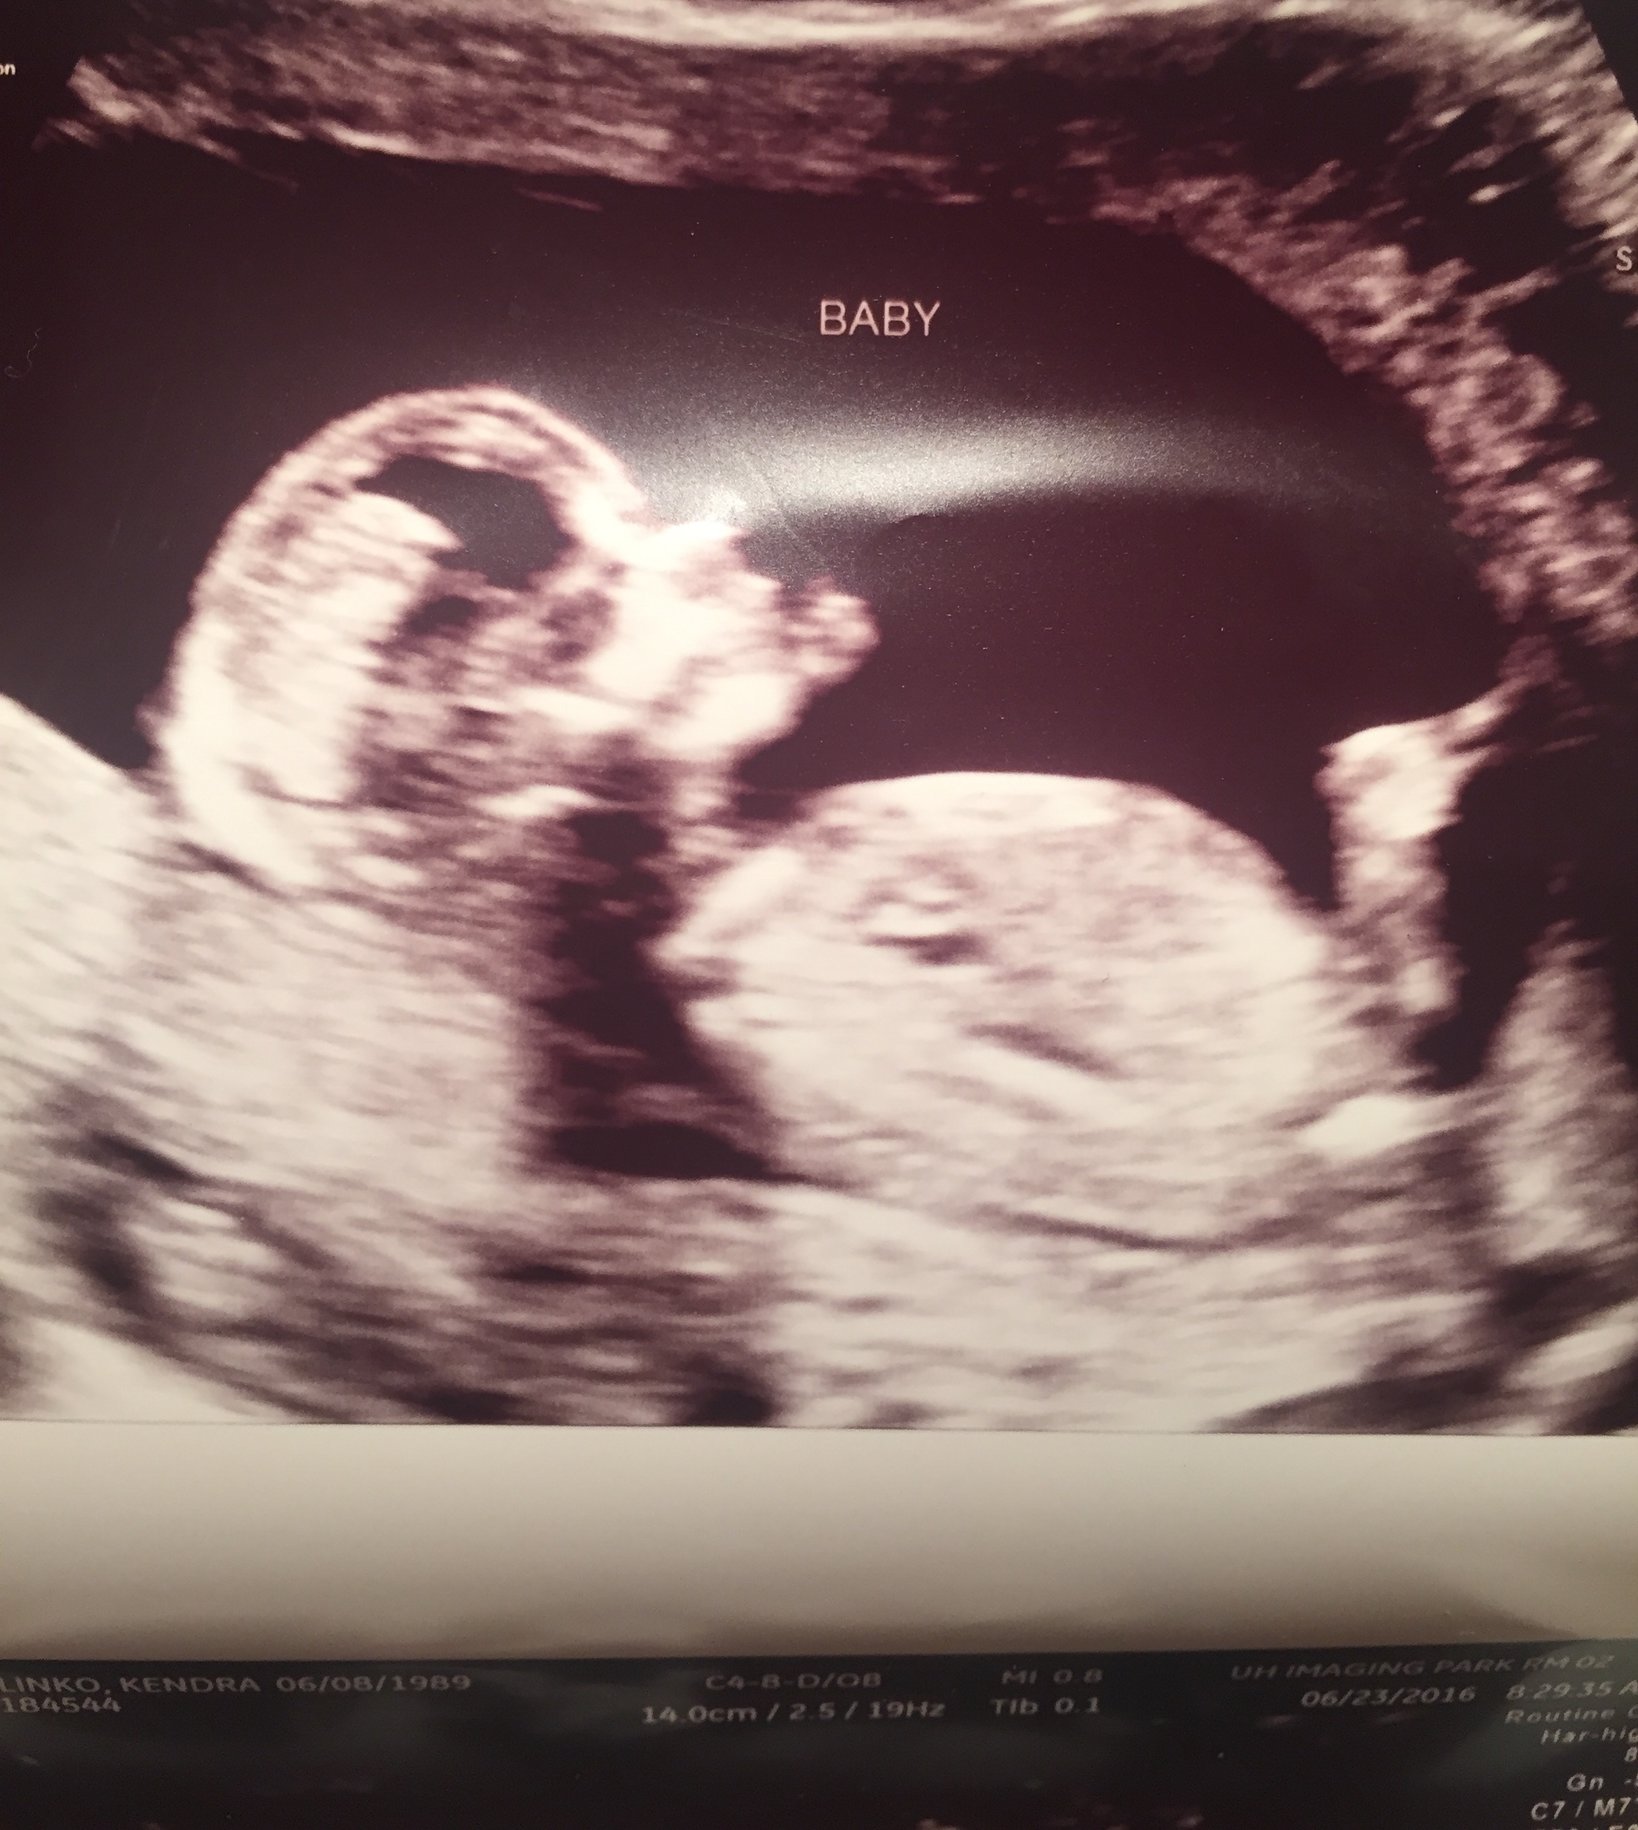

Any guesses ? I am 13 weeks and 3 days- just curious :)

• no guesses but for the love of life, please remove you personal information from the picture so internet crazies don't see this. @kpolinko89

• @kpolinko89 With this being your first ever post anywhere on this board, there not even being a visible nub, and all your personal info being posted- please take this to ingender.com. That community might suit you better.